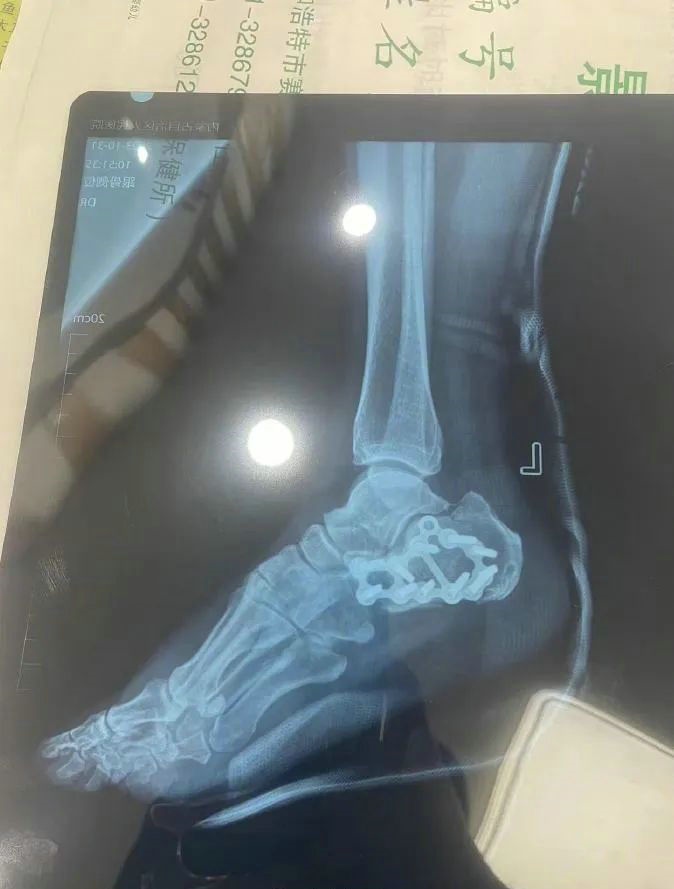

“那時候我剛工作了兩天,在第三天10月22日下午施工過程中從三層高的鐵架上摔了下來,導致30厘米左右的鋼筋刺穿我的右側(cè)臀部,左腳跟也粉碎性骨折,被送往內(nèi)蒙古自治區(qū)人民醫(yī)院救治,當晚做了手術取出刺在右臀部的鋼筋,10月30日又進行了左腳粉碎性骨折手術。”雷先生告訴記者。